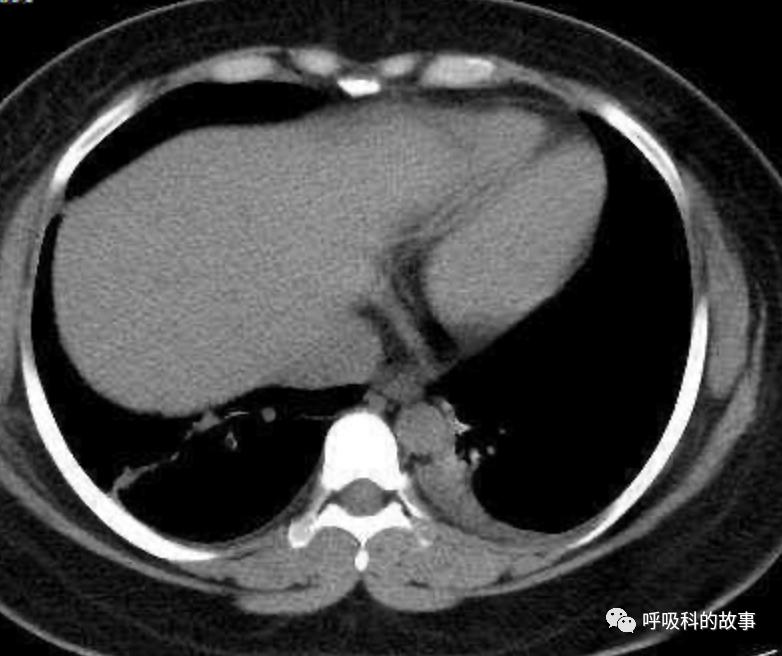

患者发热后行胸部CT检查(6月21日,住院第13天),可见两下肺有条片影,当时考虑是肺炎引起的发热。

可是在6月26日(往院第18天)仍持续发热的情况下复查肺部CT,肺部病灶已明显吸收了。那么患者发热的原因到底是什么呢?为什么患者高热的情况下血白细胞不升反降,C反应蛋白也没有明显增高?这个时候消化科医生也迷茫了,这可怎么办?于是请感染科和呼吸科医生一起会诊,共商计策。